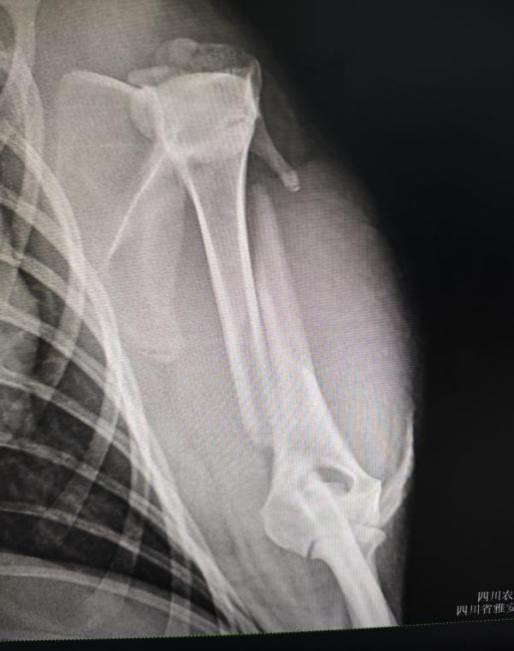

手术前左前肢腹背位X光

水豚左前肢跛行

拍摄水豚左前肢X光

水豚,一种原本生活在南美洲亚马逊河流域的珍稀哺乳动物,因其独特的生理结构和萌宠的外貌而备受关注。本次手术的主角是一只因肱骨骨折而生命垂危的水豚。经过专家团队的精心评估和准备,手术于本周初顺利进行。